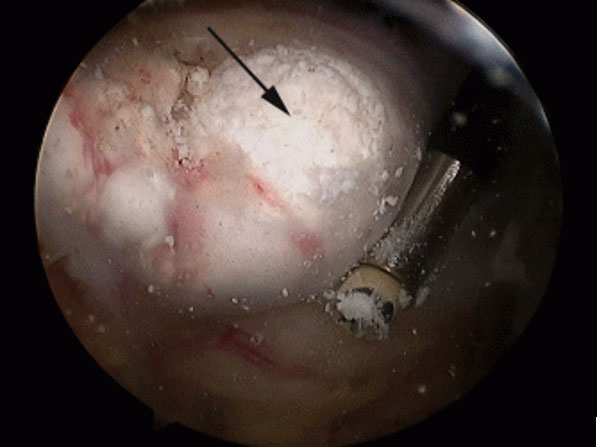

A váll meszes íngyulladásának (calcificáló tendinitis) létezik műtéti megoldása, amennyiben a konzervatív kezelés nem hoz tartós eredményt. A műtét lényege, hogy rotátorköpeny ínainak állományában felrakódott mész csomót sebészi úton kiürítjük. Az artroszkópos technikával végzett beavatkozás során rotátorköpeny külső rétegét szétválasztjuk és az alatta levő meszes ’fészeket’ alaposan kiürítjük. Előfordul, hogy az alapos mész eltávolítás érdekében az ínon nagyobb nyitást kell végezni. Ilyenkor az íngyógyulás érdekében a köpeny folytonosságát helyre kell állítani, ami a teljes felépülési időt megnyújthatja. Ezt a beavatkozást általában kiegészítjük fentiekben részletezett subacromiális decompresszióval. Rehabilitáció hozzávetőlegesen 3 hónapot is igénybe vehet.

Artroszkópos kalcium depozit kiürítés